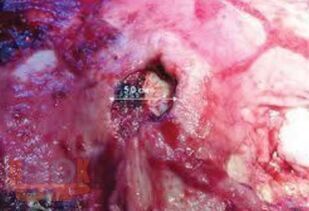

В третьей части учебного пособия «Осложнения язвенной болезни желудка и двенадцатиперстной кишки» отражены вопросы этиологии и патогенеза, классификации, клиники, диагностики, дифференциальной диагностики, консервативного и хирургического лечения язвенной болезни желудка и двенадцатиперстной кишки, осложненных пенетрацией, пилородуоденальным стенозом и малигнизацией.